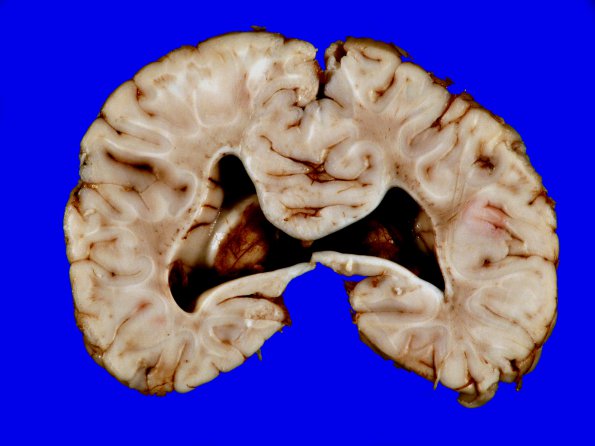

4A8 Holoprosencephaly variant & (Case 4) 17A

Additional image of cingulosynapsis.